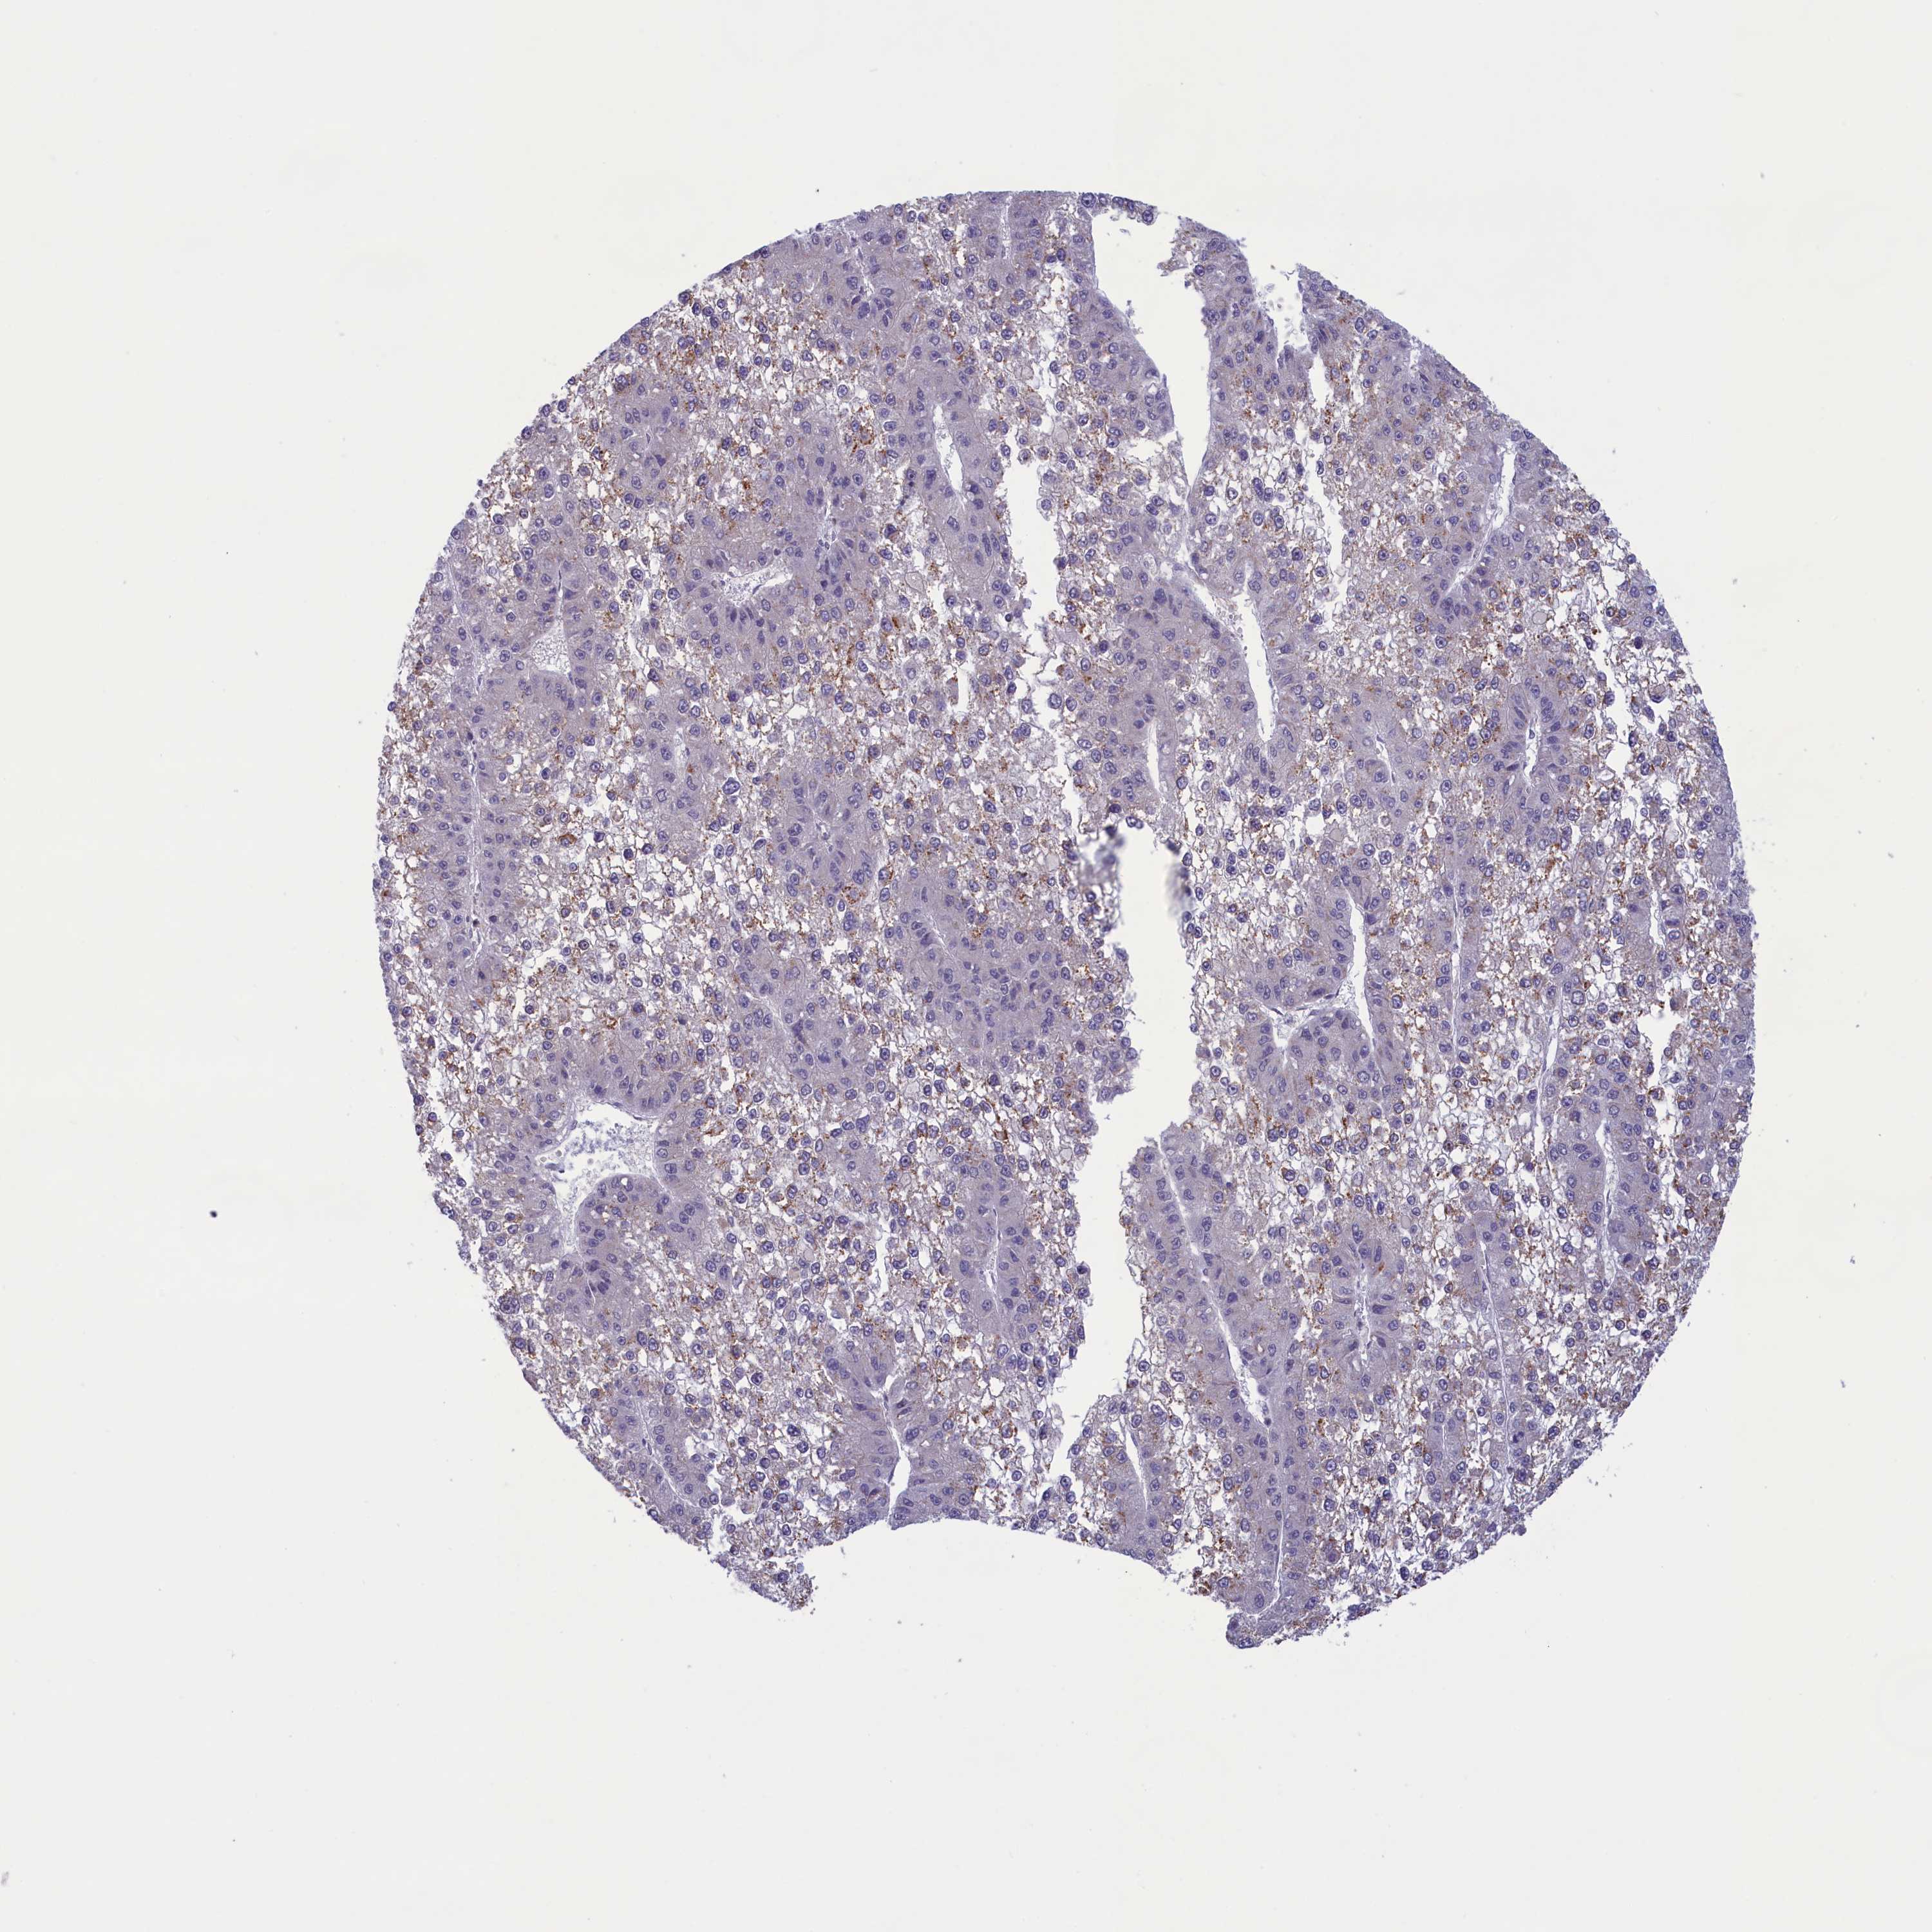

LIVER CANCER - Protein expressioni

A mouse-over function shows sample information and annotation data. Click on an image to view it in a full screen mode. Samples can be filtered based on level of antibody staining by selecting one or several of the following categories: high, medium, low and not detected. The assay and annotation is described here.

Note that samples used for immunohistochemistry by the Human Protein Atlas do not correspond to samples in the TCGA dataset.

Antibody stainingi

Antibody staining in the annotated cell types in the current human tissue is reported as not detected, low, medium, or high, based on conventional immunohistochemistry profiling in selected tissues. This score is based on the combination of the staining intensity and fraction of stained cells.

Each image is clickable and will lead to virtual microscopy that enables deeper exploration of all samples and also displays staining intensity scores, fraction scores and subcellular localization as well as patient and tissue information for each sample.

Antibody HPA041161

Antibody HPA041302

Staining

High

Medium

Low

Not detected

Intensity

Strong

Moderate

Weak

Negative

Quantity

>75%

75%-25%

<25%

None

Location

Nuclear

Cytoplasmic/membranous

Cytoplasmic/membranous,nuclear

Cholangiocarcinoma

Carcinoma, Hepatocellular, NOS